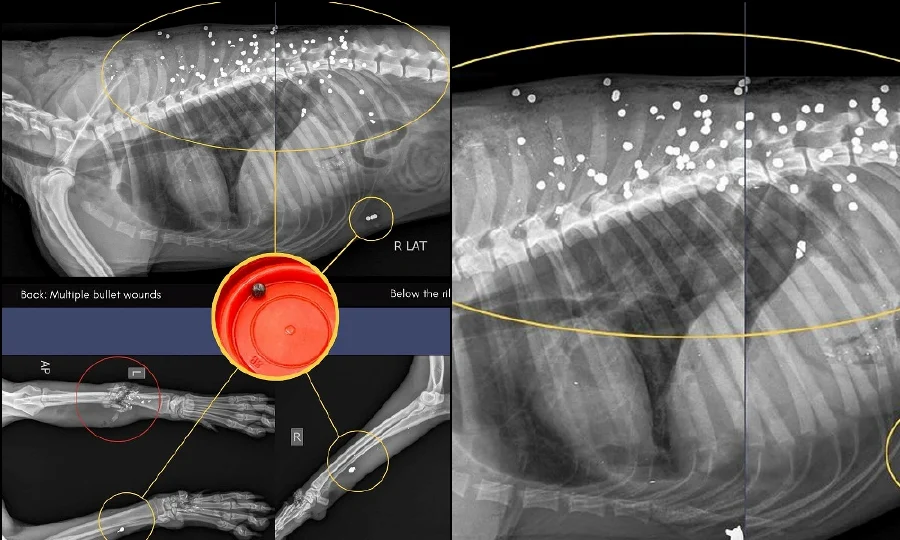

狗狗遭70颗金属弹残杀!“求线索揪虐狗者”

日前,一只流浪狗在巴生加埔被60至70颗金属弹击中后不幸身亡。